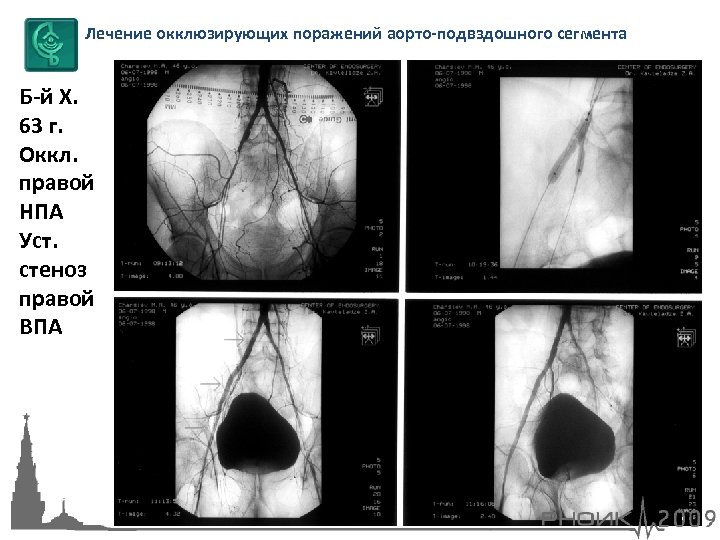

Лечение окклюзирующих поражений аорто-подвздошного сегмента Б-й Х. 63 г. Оккл. правой НПА Уст. стеноз правой ВПА